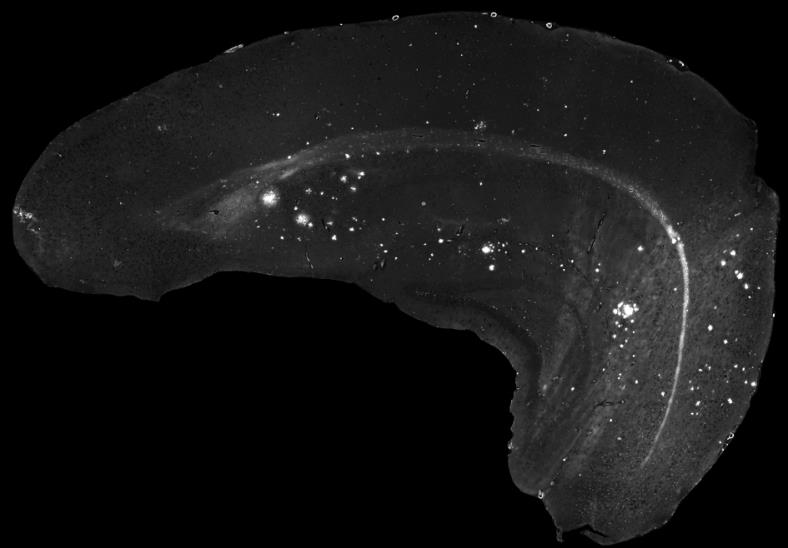

Bildunterschrift:

Im Fall der Alzheimer-Demenz entwickeln sich im Tiermodell altersabhängig Ablagerungen des Amyloid-Beta-Proteins im Gehirn. Diese können markiert und mit einem Fluoreszenzmikroskop sichtbar gemacht werden.